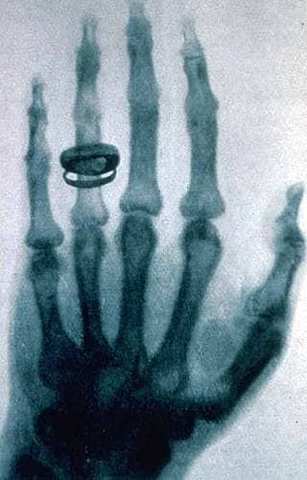

• Wilhelm Conrad Rontgen discovers medical use of X- rays in medical imaging

Wilhelm Conrad Rontgen discovers medical use of X- rays in medical imaging

Wilhelm Conrad Rontgen discovered X-rays on accident in 1895